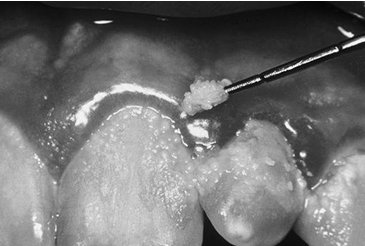

Біоплівки можуть виникнути в організмі людини як внаслідок життєдіяльності нормофлори, так і внаслідок діяльності умовно-патогеннної і патогенної мікрофлори. Бактеріальні біоплівки виявлені у ротовій порожнині, у кишечнику, на поверхні шкіри. Корисні мікроорганізми утворюють організовані співтовариства, так само, як і шкідливі мікроорганізми. Наприклад, корисна мікрофлора кишечника відповідальна за активність імунітету, лактобактерії вагінального середовища перешкоджають інфікуванню плоду під час нормального ходу вагітності. Крім того, сапрофітні бактерії мають здатність перешкоджати адгезії і колонізації патогенних мікроорганізмів.

Однак, на даний момент вивчена роль і значення бактеріальних біоплівок у етіології та патогенезі багатьох гострих, і особливо, хронічних бактеріальних інфекцій людини. До таких захворювань відносять інфекції сечових шляхів, інфекції середнього вуха ( H.influenzae), муковісцидоз, кістозний фіброз (P.аeruginosa), інфекційний ендокардит, інфекції протезних клапанів, катетор-асоційовані інфекції кровоточу (коагулазопозитивні і коагулазонегативні стафілококи) та стоматологічні проблеми (карієс, парадонтит, гінгівіт). Враховуючи опубліковані дані, частота інфекцій, зумовлених біоплівкою, складає 65 -80%.

Нині доведена участь біоплівок вконтамінації медичних імплантатів. Найчастішебіоплівки формуються на катетерах (серцевих, вну-трішньовенних, сечовивідних), штучних клапанахсерця (будучи головною причиною інфекційних эндокардитів), штучних суглобах, контактних лінзах(часто будучи причиною кератитів). Хронічні інфекції імплантованих медичних пристроїв можуть призвести до розвитку сепсису і смерті пацієнтів, особливо у осіб з ослабленим імунітетом, тому розвиток мікробних біоплівок на синтетичних імплантатах є великою проблемою для їх успішного впровадження і ефективного функціонування. Видовий склад біоплівок переважно представлений:S.aureus, Enterococcus, Streptococcus, KlebsiellaPseudomonas, E.coli. Крім того, багато патогеннів, як, наприклад Salmonella, E.coli, Y.enterocalitica, Listeria, Campylobacter, існують у вигляді біоплівок на поверхні харчових продуктів або на поверхні устаткування для їх зберігання.

Рис. 7 Зубний наліт, як приклад біоплівки ротової порожнини

Рис. 8 БіоплівкаS.epidermidis з клапану серця при інфекційному ендокардиті